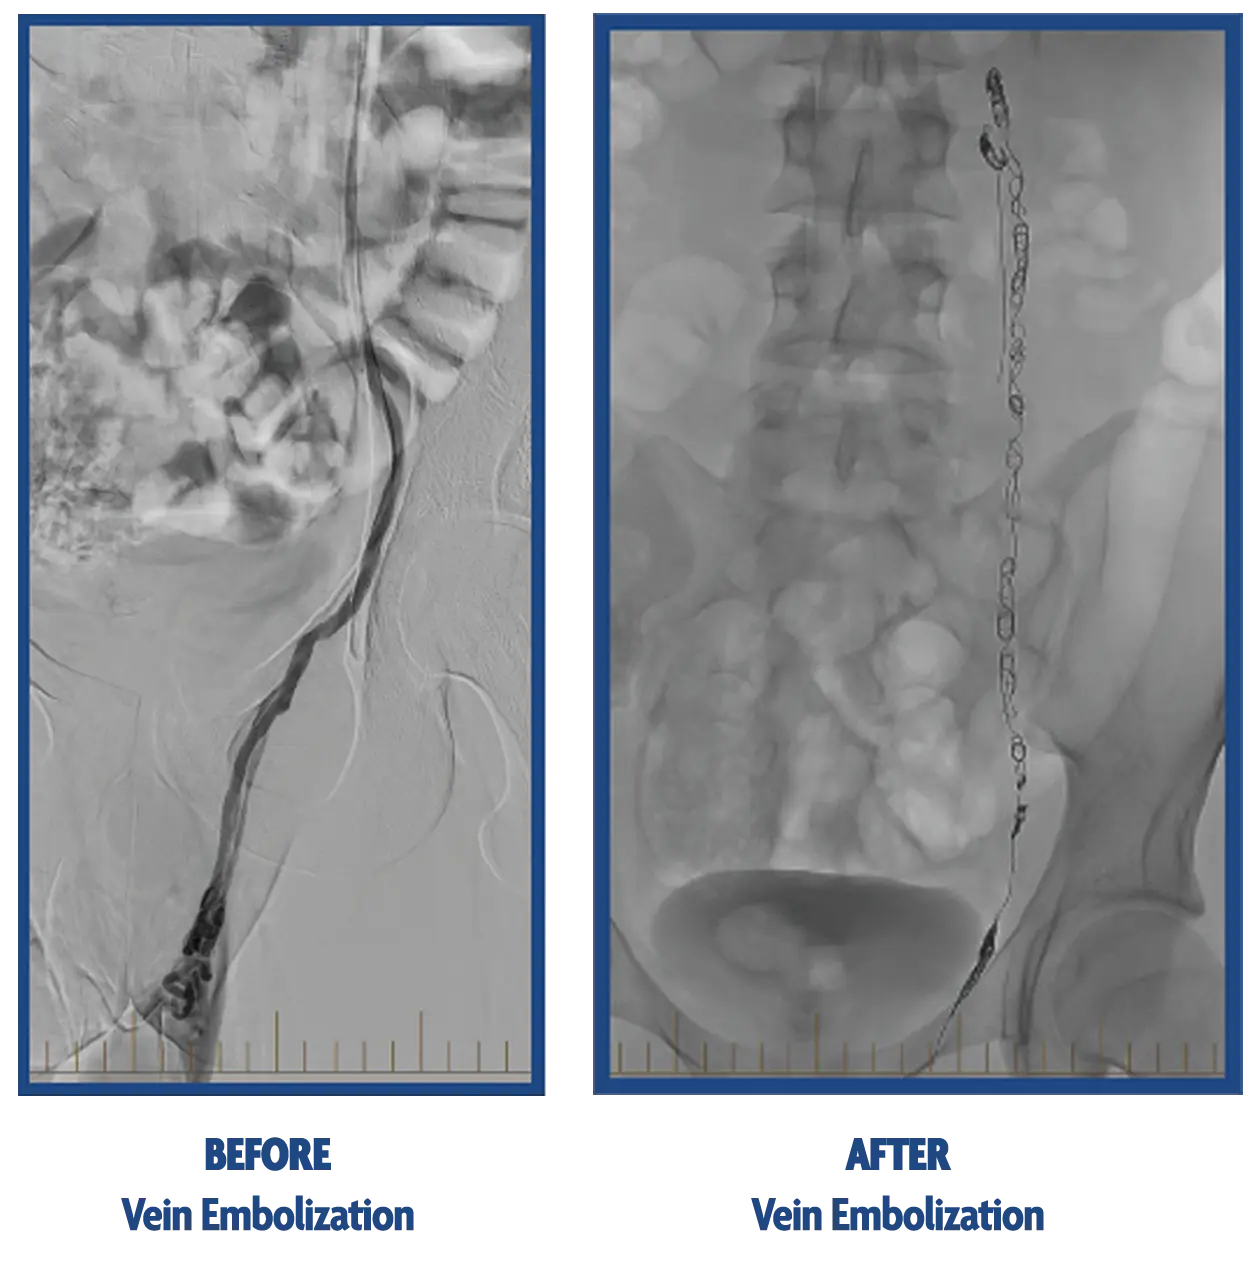

Vein Embolization

- Using an x-ray camera, a small catheter is then guided into the veins supplying the scrotum.

- A vein irritant (which burns the veins) along with small coils are placed within the enlarged, unhealthy veins to stop blood supply to them.